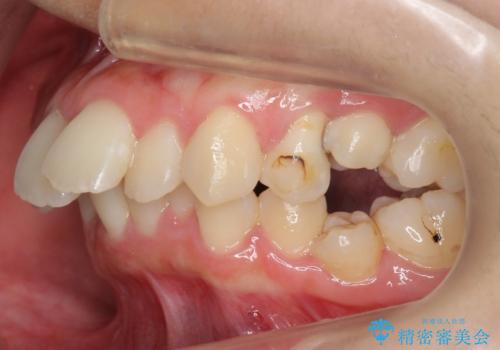

[40代女性] 口元を引っ込めたい 大きく改善

- 口元の突出感を気にして来院。

ガタつきは少ないですが、上下前歯が前方に突出した、上下顎前突でした。

下の前歯を支える骨が薄く、歯肉退縮のリスクがありました。

抜歯して前歯を後方に下げる治療を希望されたため、様子を見ながら移動をしていくことにしました。

上下小臼歯を抜歯しています。

![[40代女性] 口元を引っ込めたい 大きく改善の治療中](https://seimitsushinbi.jp/wp/wp-content/uploads/2018/01/C67-500x350.jpg)

![[40代女性] 口元を引っ込めたい 大きく改善の治療中](https://seimitsushinbi.jp/wp/wp-content/uploads/2018/01/C68-500x350.jpg)